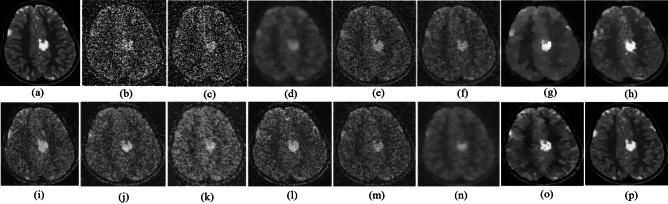

Medical imaging systems such as computed tomography (CT) and magnetic resonance imaging (MRI) are vital tools in clinical diagnosis and treatment planning. However, these modalities are inherently susceptible to Gaussian noise introduced during image acquisition, leading to degraded image quality and impaired visualization of critical anatomical structures. Effective denoising is therefore essential to enhance diagnostic accuracy while preserving fine details such as tissue textures and structural boundaries. This study proposes a robust and efficient denoising framework specifically designed for CT and MRI images corrupted by Gaussian noise. The method integrates a cluster-wise principal component analysis (PCA) thresholding approach guided by the Marchenko-Pastur (MP) law from random matrix theory and a non-local means algorithm. Noise level estimation is achieved globally by analysing the statistical distribution of eigenvalues from noisy image patch matrices and leveraging the MP law to accurately determine the Gaussian noise variance. An adaptive clustering technique is employed to group similar patches based on underlying features such as textures and edges and enables localized denoising operations tailored to heterogeneous image regions. Within each cluster denoising is performed in two stages where initially hard thresholding based on the MP law is applied to the singular values in the SVD domain to obtain a low-rank approximation that preserves essential image content while removing noise-dominated components. Residual noise in the low-rank matrix is then further suppressed through a coefficient-wise linear minimum mean square error LMMSE estimator in the PCA transform domain. Finally, a non-local means algorithm refines the denoised image by computing weighted averages of pixel intensities and prioritizing neighbourhood similarity over spatial proximity to effectively preserve edges and textures while reducing Gaussian noise. Experimental evaluations on CT and MRI datasets demonstrate that the proposed method achieves superior denoising performance while maintaining high structural similarity and perceptual quality compared to existing state-of-the-art approaches. The method demonstrates adaptability noise reduction capability and preservation of anatomical detail that make it well suited for precision critical medical imaging applications.

计算机断层扫描(CT)和磁共振成像(MRI)等医学成像系统是临床诊断和治疗规划中的重要工具。然而,这些模态在图像采集过程中固有地容易受到高斯噪声的影响,导致图像质量下降以及关键解剖结构的可视化受损。因此,有效的去噪对于提高诊断准确性同时保留诸如组织纹理和结构边界等精细细节至关重要。本研究提出了一种强大且高效的去噪框架,专门针对受高斯噪声破坏的CT和MRI图像设计。该方法集成了一种由随机矩阵理论中的马尔琴科 - 帕斯图尔(MP)定律引导的聚类主成分分析(PCA)阈值处理方法和一种非局部均值算法。通过分析噪声图像块矩阵的特征值统计分布并利用MP定律来准确确定高斯噪声方差,实现全局噪声水平估计。采用自适应聚类技术根据纹理和边缘等潜在特征对相似块进行分组,并针对异质图像区域进行局部去噪操作。在每个聚类中,去噪分两个阶段进行,首先在奇异值分解(SVD)域中基于MP定律应用硬阈值处理奇异值,以获得保留基本图像内容同时去除噪声主导成分的低秩近似。然后在PCA变换域中通过系数线性最小均方误差(LMMSE)估计器进一步抑制低秩矩阵中的残余噪声。最后,非局部均值算法通过计算像素强度的加权平均值并优先考虑邻域相似性而非空间邻近性来细化去噪图像,从而在减少高斯噪声的同时有效保留边缘和纹理。对CT和MRI数据集的实验评估表明,与现有的最先进方法相比,所提出的方法在保持高结构相似性和感知质量的同时实现了卓越的去噪性能。该方法展示了适应性降噪能力和解剖细节保留能力,使其非常适合精密关键的医学成像应用。